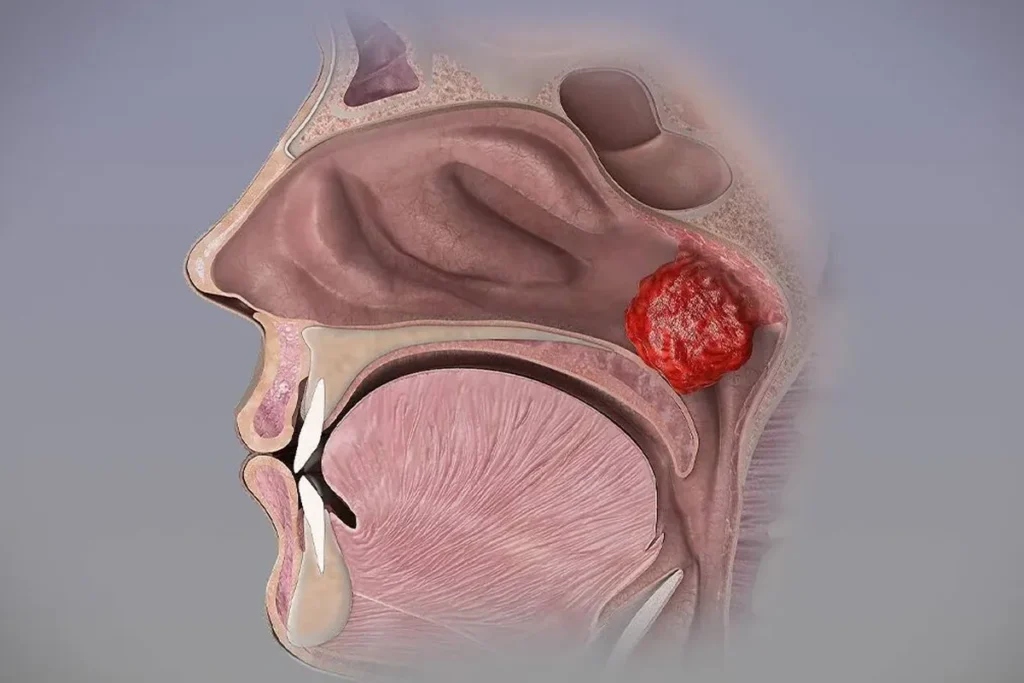

Bademcikler (tonsiller), boğazın her iki yanında bulunan…

Geniz Eti Koblasyon Ameliyatı Nedir? Belirtileri, Tedavisi…